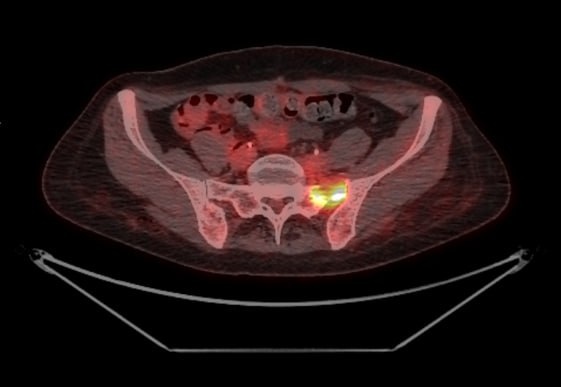

В 2021 году в возрасте 54 лет у пациентки диагностировали редкую и агрессивную форму рака шейки матки — муцинозный рак (встречается в 0.1% случаев). Несмотря на проведенное лечение (лучевая терапия и сложнейшая операция), болезнь прогрессировала: возникли проблемы с почками и кишечником, потребовались новые операции (стентирование мочеточников, сигмостомия).

К лету 2023 года обнаружились множественные метастазы. Пациентке была рекомендована симптоматическая терапия, и её направили в хоспис.

В августе 2023 года в крайне тяжелом состоянии (ECOG 3-4) пациентка поступила в Ильинскую больницу. Мы боролись вместе: проводили курсы химио-, иммуно- и таргетной терапии.

В августе 2024 года болезнь прогрессировала — появились метастазы в печени. Однако в опухолевой ткани выявлена амплификация HER2/neu, что позволило нам изменить терапию.

Дав пациентке новый эффективный препарат, мы добились ответа:

🔹 Ушли сильные боли.

🔹 ECOG улучшился с 3-4 до 1 — пациентка снова начала ходить и набирать вес.

🔹 Метастазы в печени значительно уменьшились.